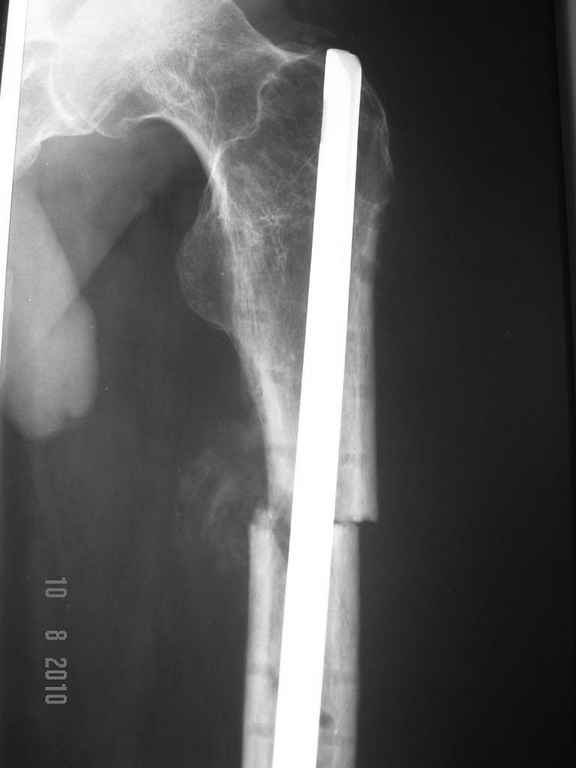

ДОбавил фото....

Условия больницы не блещут как собственно и финансовые возможности больного. Варианты типа БИОС, бусы с антибиотиками наверное так и останутся "вариантами". Пока интересует вопрос - остеомиелит? что делать?